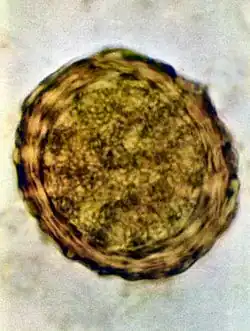

Ascaris lumbricoides is characterized by its great size. Males are 2–4 mm (0.08–0.2 in) in diameter and 15–31 cm (5.9–12 in) long. The male's posterior end is curved ventrally and has a bluntly pointed tail. Females are 3–6 mm (0.1–0.2 in) wide and 20–49 cm (7.9–19 in) long. The vulva is located in the anterior end and accounts for about one-third of its body length. Uteri may contain up to 27 million eggs at a time, with 200,000 being laid per day. Fertilized eggs are oval to round in shape and are 45–75 μm (0.0018–0.0030 in) long and 35–50 μm (0.0014–0.0020 in) wide with a thick outer shell. Unfertilized eggs measure 88–94 μm (0.0035–0.0037 in) long and 44 μm (0.0017 in) wide.[9]